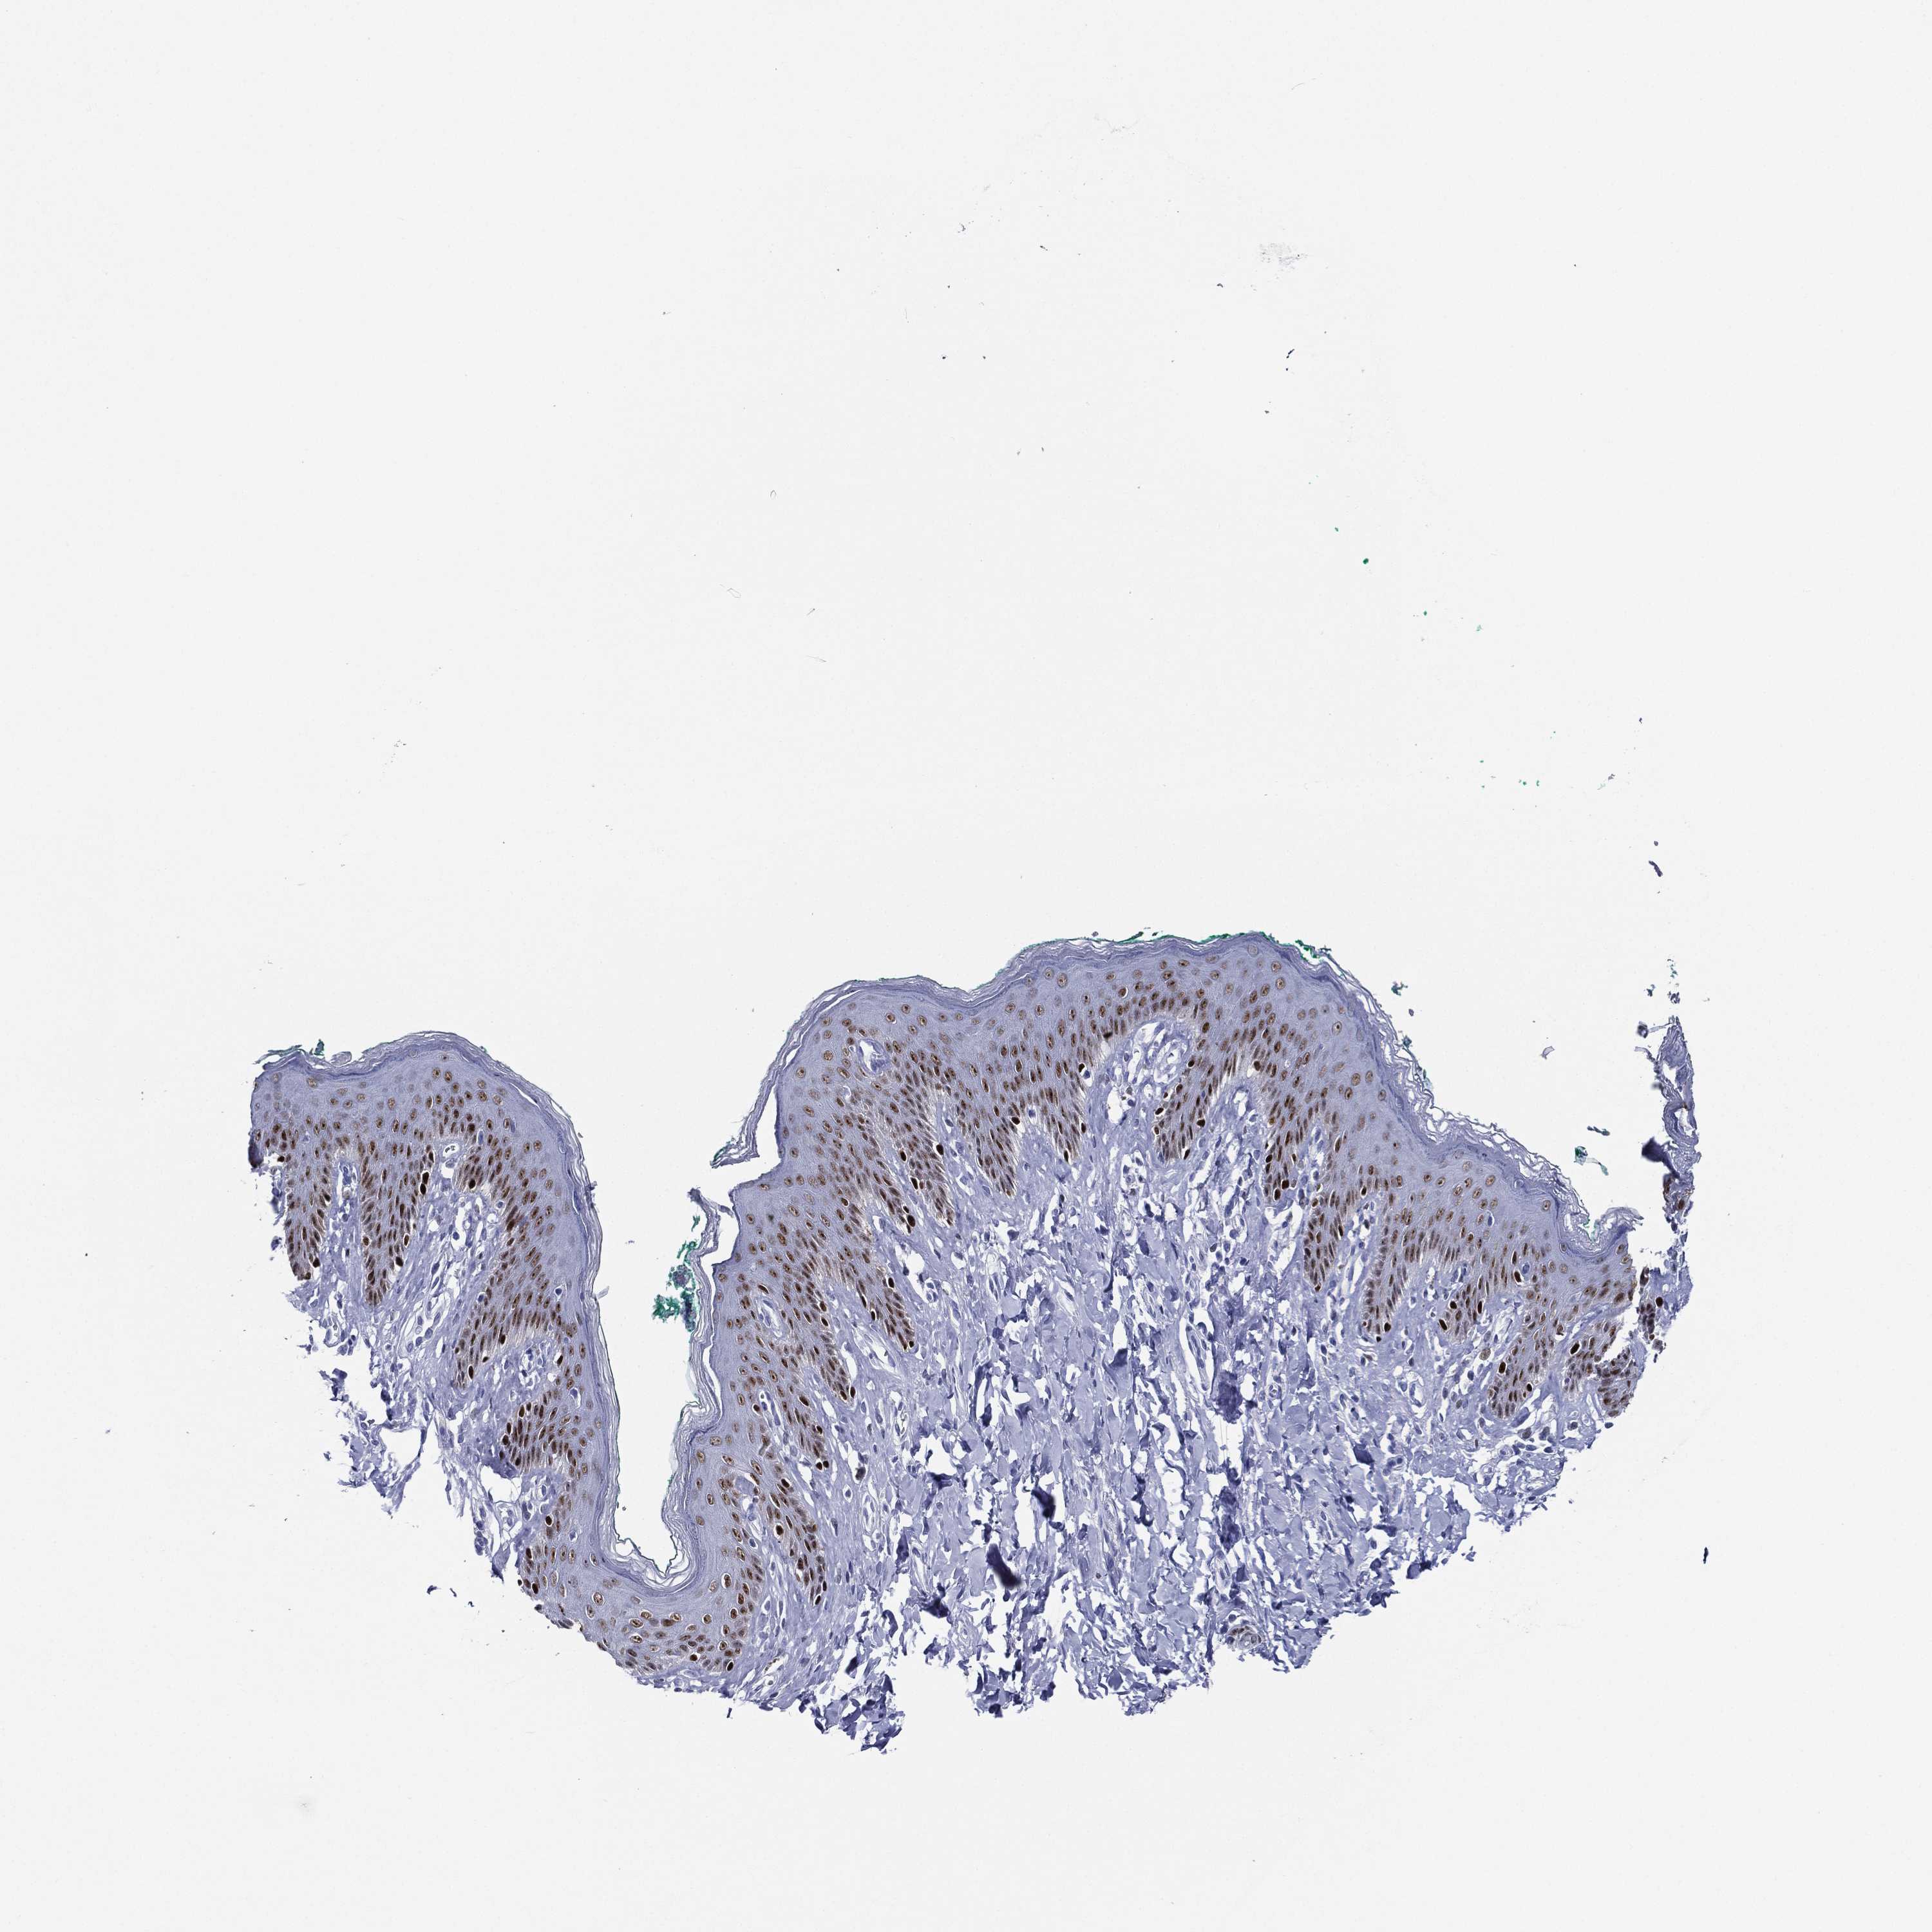

SKIN 2 - Antibody stainingi

Antibody staining in the annotated cell types in the current human tissue is reported as not detected, low, medium, or high, based on conventional immunohistochemistry profiling in selected tissues. This score is based on the combination of the staining intensity and fraction of stained cells.

Each image is clickable and will lead to virtual microscopy that enables deeper exploration of all samples and also displays staining intensity scores, fraction scores and subcellular localization as well as patient and tissue information for each sample.

Antibody HPA056871Antibody CAB000326

Cells in basal layer -Medium

Cells in corneal layer -Not detected

Cells in granular layer -Low

Cells in spinous layer -Medium

Endothelial cells -Not detected

Epidermal cells Medium-

Extracellular matrix -Not detected

Fibrohistiocytic cells -Not detected

Langerhans cells -Medium

Lymphocytes -Not detected

Melanocytes -High

Vascular mural cells -Not detected